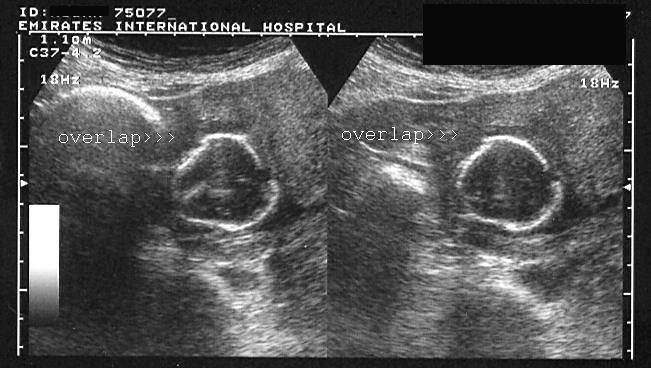

Monochorionic, monoamniotic twin gestation